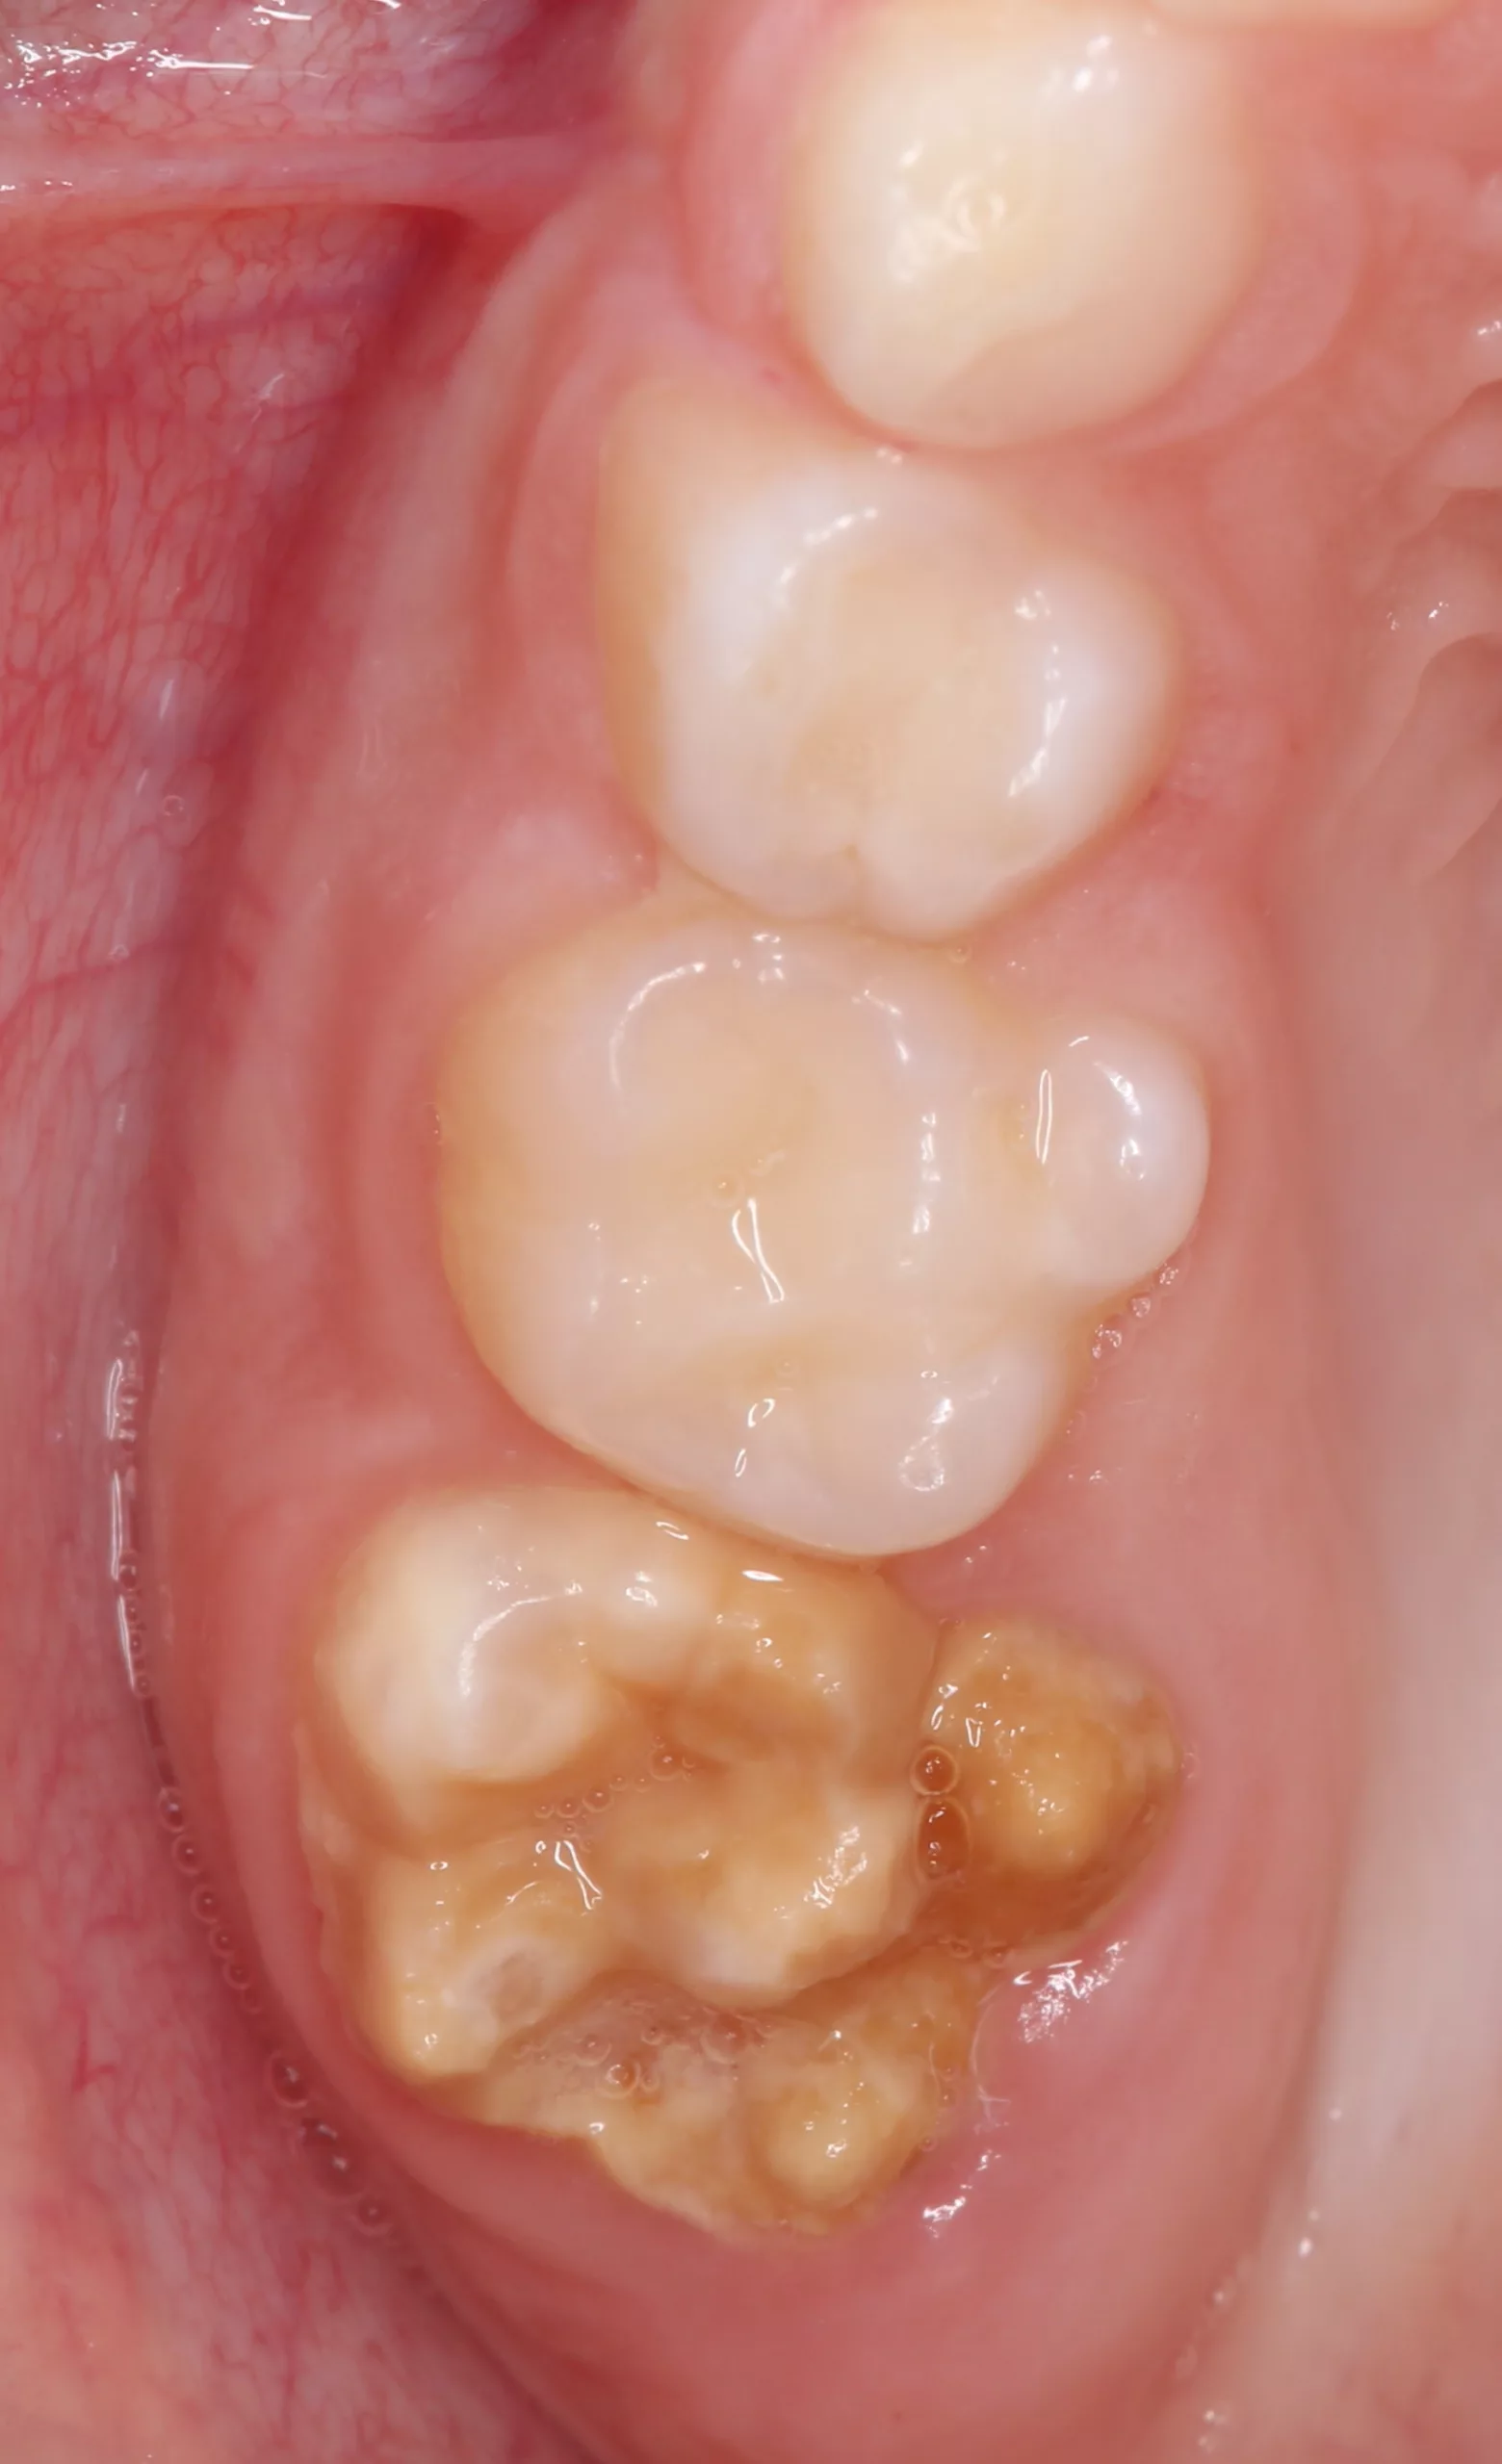

Der Begriff der „Molaren-Inzisiven-Hypomineralisation“ wird seit dem Kongress der European Academy of Paediatric Dentistry (EAPD) [1] im Jahre 2001 verwendet. Dieser beschreibt eine systemisch bedingte Hypomineralisation von ein bis vier bleibenden ersten Molaren mit oder ohne Beteiligung der Inzisiven [2] (Abb. 1 u. 2).

Klinisch imponieren die betroffenen Zähne durch abgegrenzte, weiß-cremige bis gelb-braune Verfärbungen bis hin zu prä- und posteruptiv entstandenen Schmelzdefekten mit zum Teil ausgeprägten Porositäten [2, 3]. Die Molaren sind dabei häufiger und ausgeprägter befallen als die Schneidezähne. Zu ergänzen ist, dass das klassische Bild des Befalls der Molaren und Inzisiven in der Zwischenzeit korrigiert wurde, da vereinzelt als MIH beschriebene Defekte mittlerweile auch an anderen Zähnen der bleibenden Dentition (7er, 5er, 3er) beobachtet worden sind. Des Weiteren finden sich vermehrt auch Hypomineralisationen an den zweiten Milchmolaren und den Milcheckzähnen [4, 5].

Im Alltag zeigen sich die klinischen Manifestationen von MIH in den verschiedensten Bildern und Zuständen. Für eine Einteilung in Schweregrade eignet sich die Klassifikation nach Wetzel und Reckel [19]:

- Grad I: einzelne cremefarbene bis braune Areale an Kauflächen/Höckerspitzen bei erhaltener Zahnmorphologie (Abb. 3)

- Grad II: überwiegend gelb-brauner Zahnschmelz, hypomineralisierte Bereiche über die Okklusalfläche hinaus bei erhöhter Gefahr für Schmelzfrakturen und gesteigerter Empfindlichkeit der betroffenen Zähne

- Grad III: große gelblich-braune Areale im gesamten Zahnbereich mit Defekten in der Kronenmorphologie und starken Schmelzverlusten, gekoppelt mit einer hohen Empfindlichkeit der Zähne (Abb. 4)